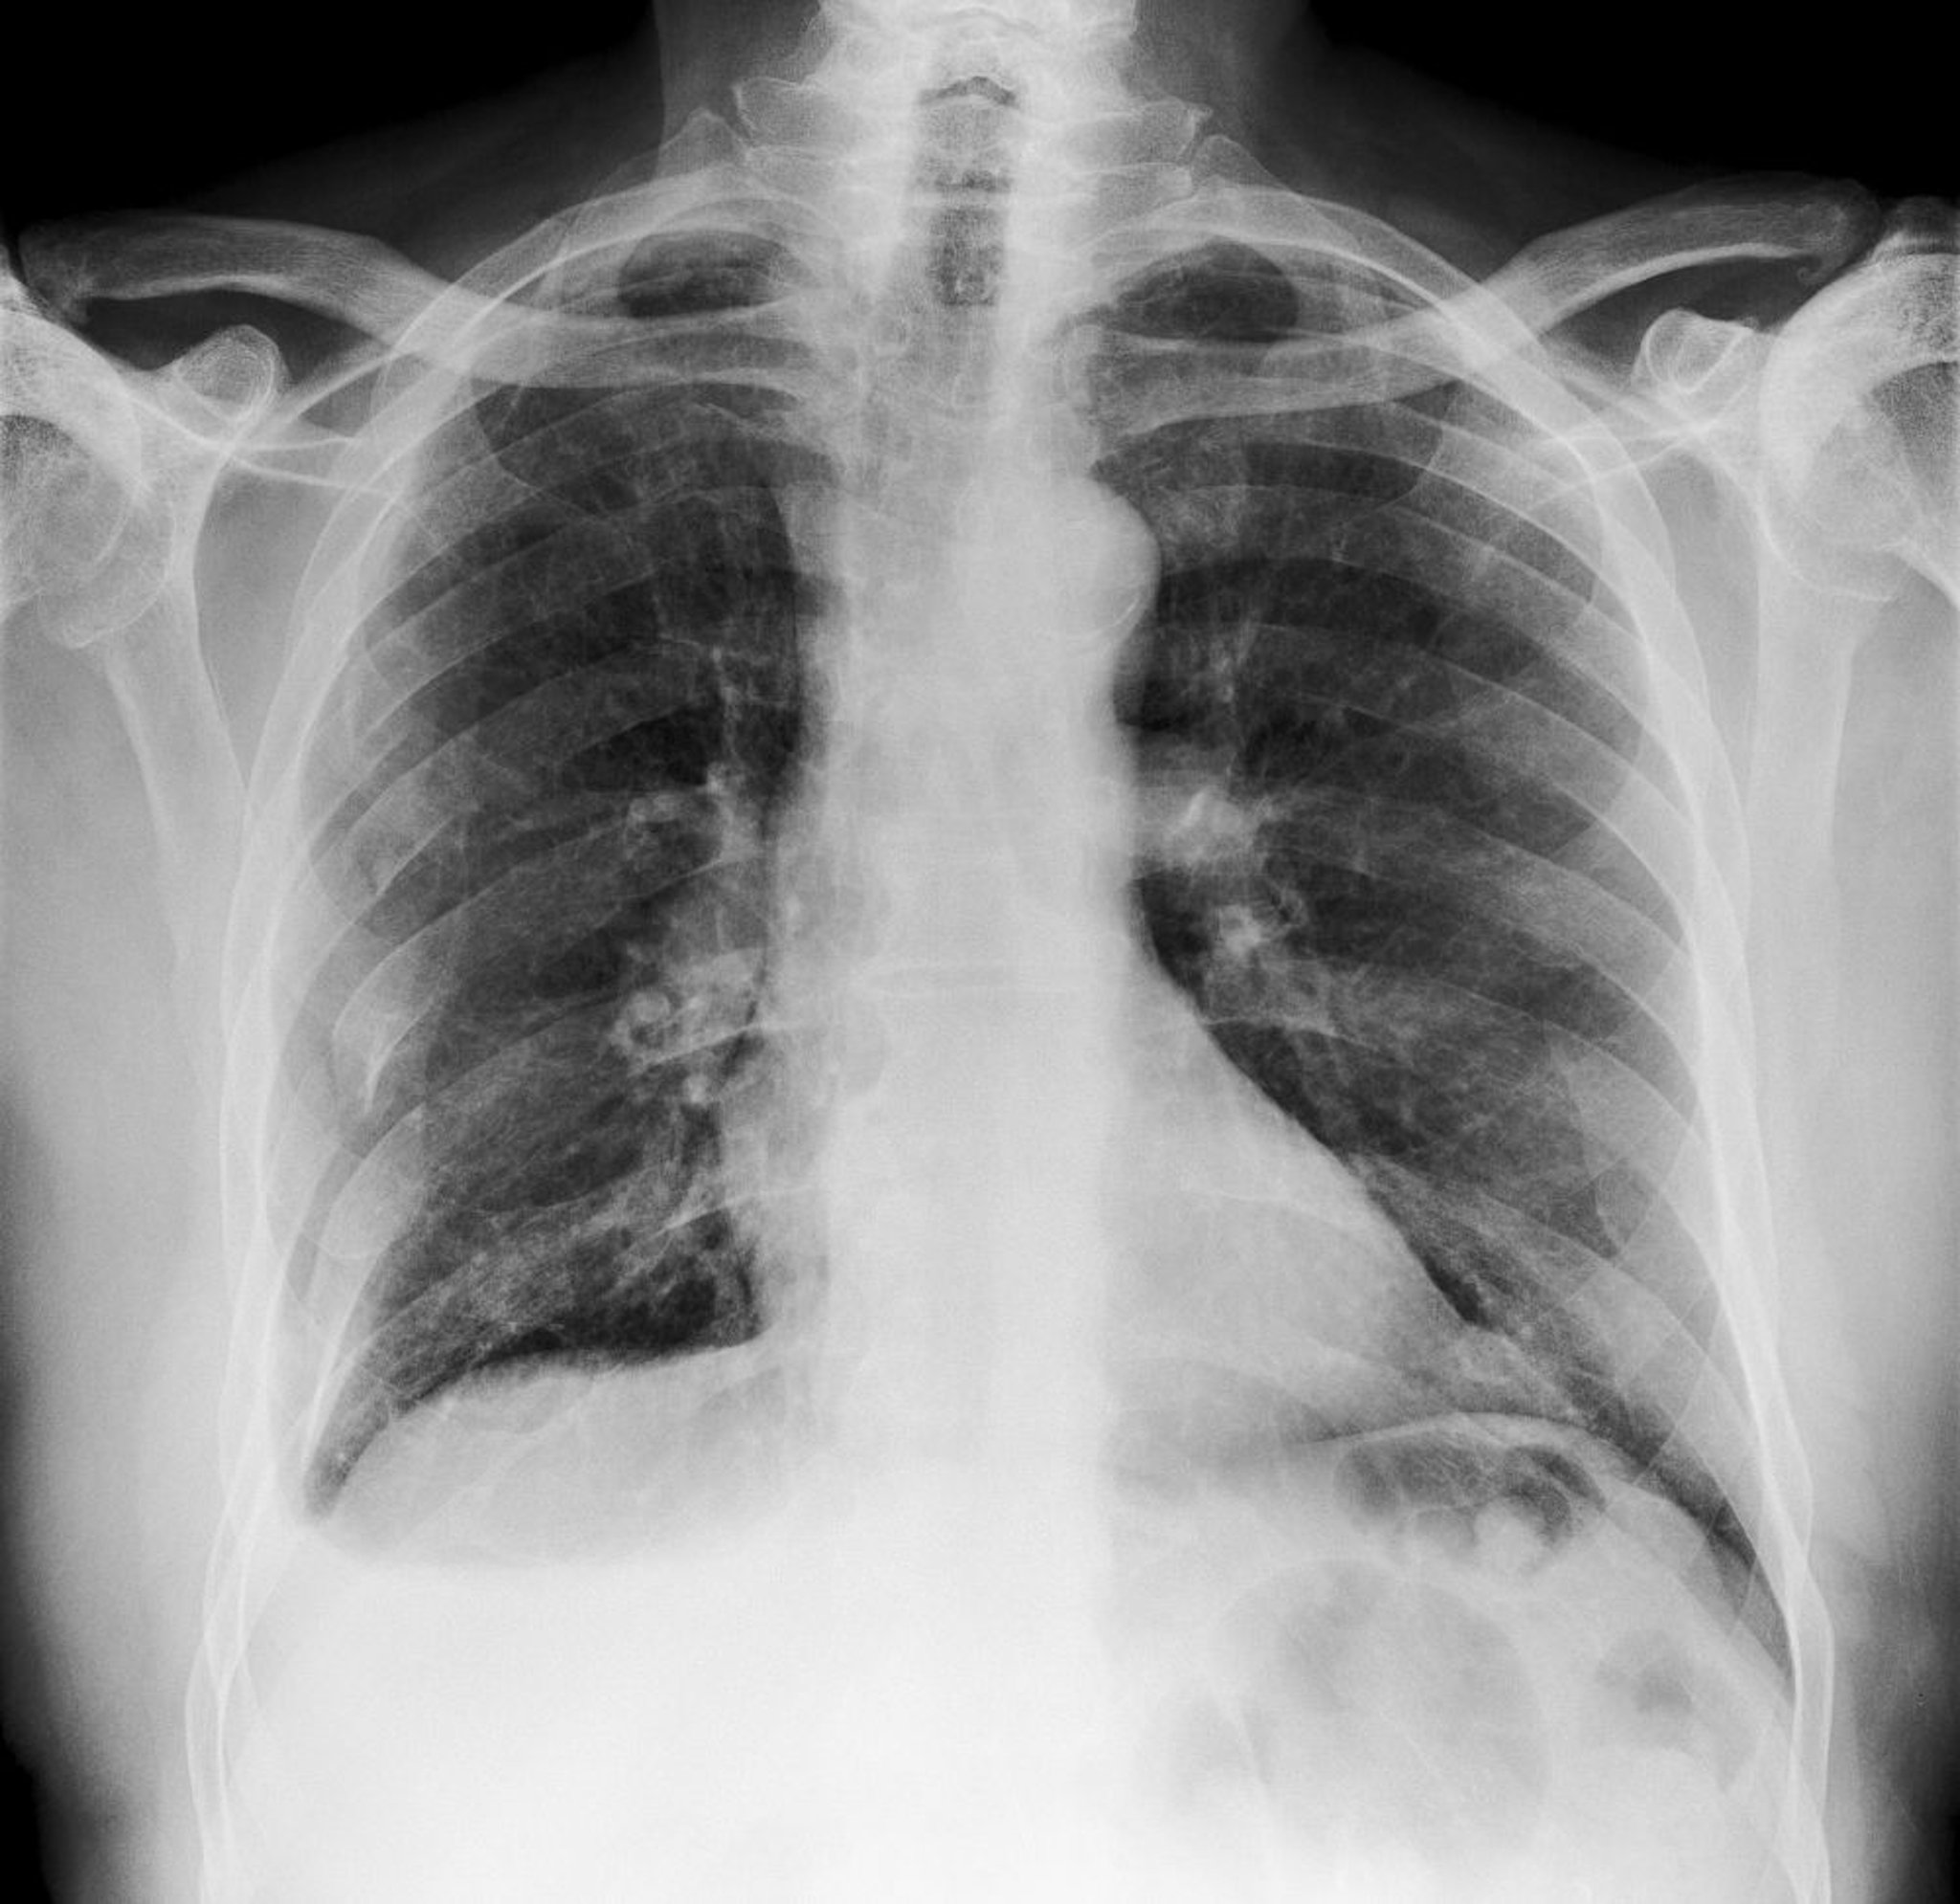

Questa radiografia del torace mostra fratture multiple alle costole destre (visibili a sinistra).